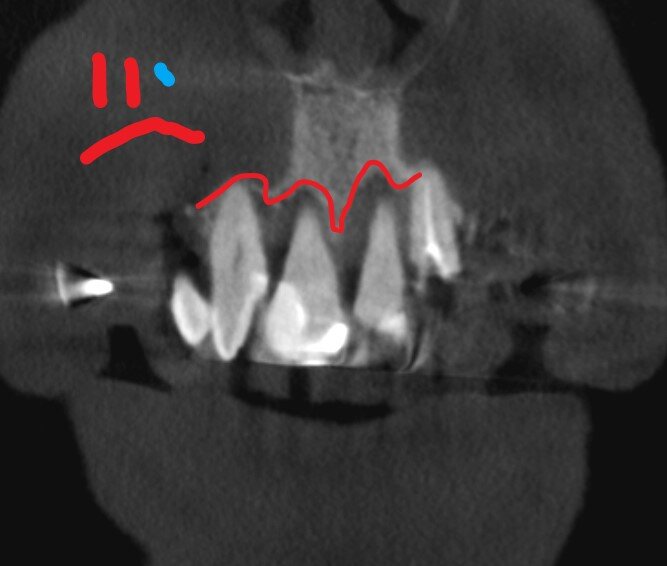

Первая половина операции прошла довольно бодро. А потом сюрприз - один из боковых имплантатов под угрозой, никак не пилится для него доступ. Сверло будто во что-то упирается. Варианты:

• плотнейшая кость;

• упёрлись в нёбную кость;

• упёрлись во что-то иное - в пин.

Прямо очень хорошо, что в клинике есть аппарат КЛКТ - тут же делаем снимок.

Места - навалом. Препятствий нет. Путь безопасен - доктор берёт другие свёрла и потихоньку продвигается. Успешно.

Признаётся, что без снимка работа была бы слишком рискованной - но пришлось бы её завершать в слепую. Ужас-ужас. Пациента на полпути никуда не денешь, не отпустишь.